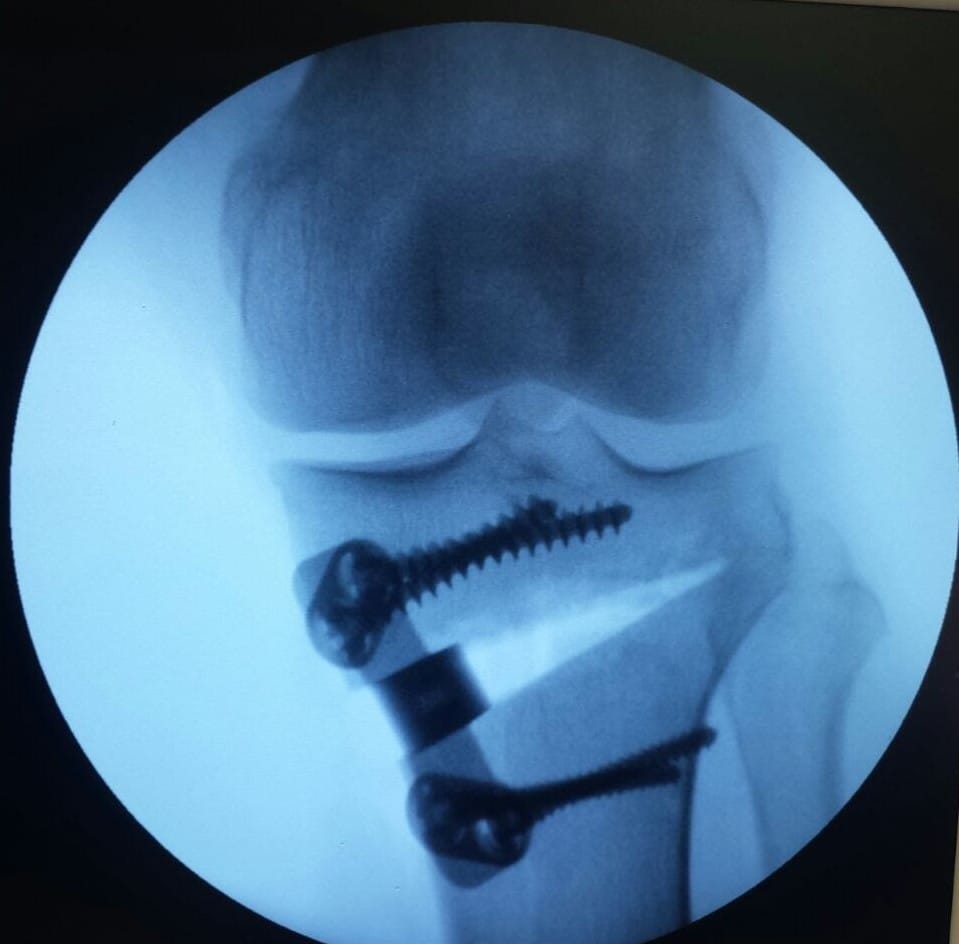

Osteotomia

A osteotomia do joelho é um procedimento cirúrgico indicado principalmente para pacientes com desalinhamento do eixo do membro inferior, frequentemente em casos de artrose em estágio inicial ou moderado, localizada em um dos compartimentos do joelho.

O objetivo da cirurgia é redistribuir a carga que passa pela articulação, aliviando a pressão na área lesionada e preservando o joelho natural por mais tempo.